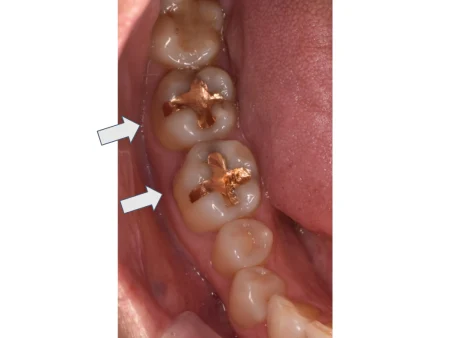

セラミック 2023.0330代女性「ゴールドの詰め物を白くしたい」金属で治療した歯を、目立ちにくい白さで強度もあるセラミックの詰め物「E-maxインレー」に替えて自然な見た目にした症例